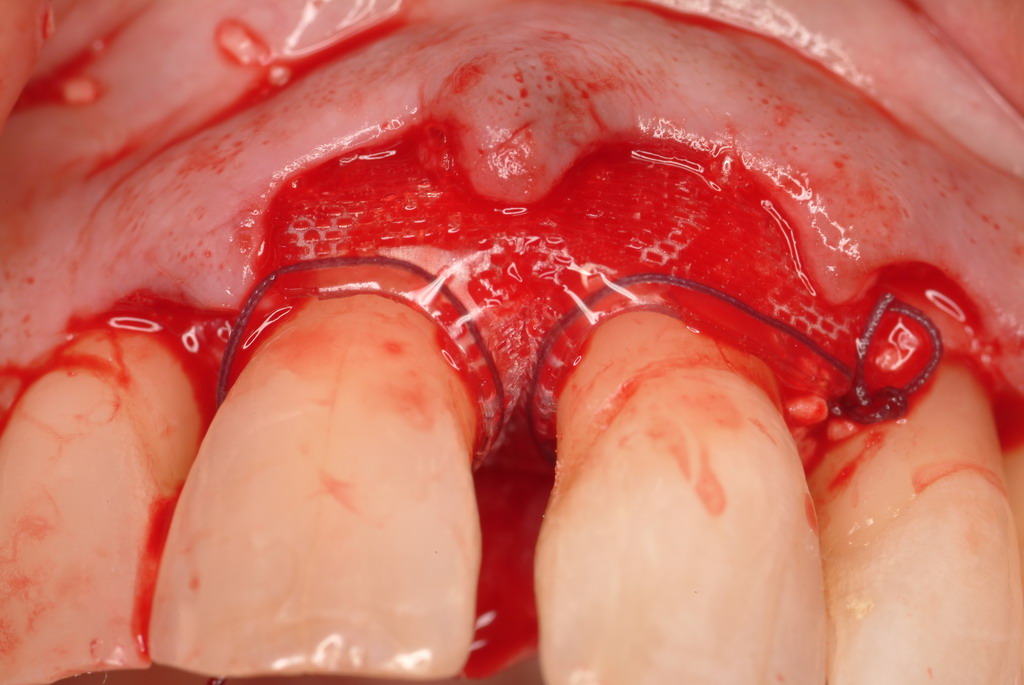

The patient had been referred for an implant consultation for the mandibular right canine. She had very deep probing depths on the lingual. When the flap was raised, a significant amount of subgingival calculus was seen as a local risk factor (Figure 18). However, she had no significant pathology to remove from the situation. Debridement was performed the same as in Case 3 with the rotary ultrasonic and manual instrumentation.

The defect was obturated with mineralized freeze-dried bone and hydrated with platelet-derived growth factor. As with any growth factor, when implementing it clinically, all growth factors require a carrier to bring that growth factor to the desired site, which do not elicit an inflammatory response. In this situation, it is the mineralized freeze-dried bone allograft. This combination was demonstrated by Rosen et al8 to be efficacious in treating intrabony defects. A biologic approach was taken both in terms of the graft and membrane (Figure 19). Primary closure was achieved.

A resorbable membrane sutured around the teeth bordering the intrabony defect.

Figure 15

Subgingival calculus and severe bone loss.

Figure 18